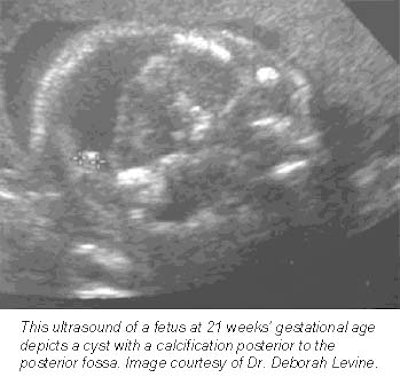

An example of MRI’s newfound obstetric niche can be found at New York City’s Mount Sinai School of Medicine, where radiologists often use the modality to better image cranial masses that are difficult to diagnose solely with ultrasound, according to a report presented at the 2001 American Institute of Ultrasound in Medicine meeting.

Still more applications are being pioneered at Boston’s Beth Israel Deaconess Medical Center, where researchers are nearing the end of a five-year study funded by the National Institutes of Health to evaluate how MRI complements prenatal ultrasound in the diagnosis of central nervous system disorders. So far, their results are promising.

"MR almost always will make you more sure of your diagnosis," said associate professor of radiology Dr. Deborah Levine. "It informs how we counsel the patient. Sometimes it directs the mode and timing of delivery, or helps a patient decide whether to terminate a pregnancy."

Levine, who oversees about one prenatal MRI exam per week, said she finds the modality especially helpful in determining whether fetuses suffer from central nervous system anomalies, as well as for defining many chest masses. Some radiologists are also using MRI to get a better idea of fetal volume, particularly in abnormal fetuses that are either too large or too small, she said.

Basically, MR is helpful whenever ultrasound is unclear, Levine said -- a general rule of thumb that’s allowed the procedure to catch on at institutions nationwide.